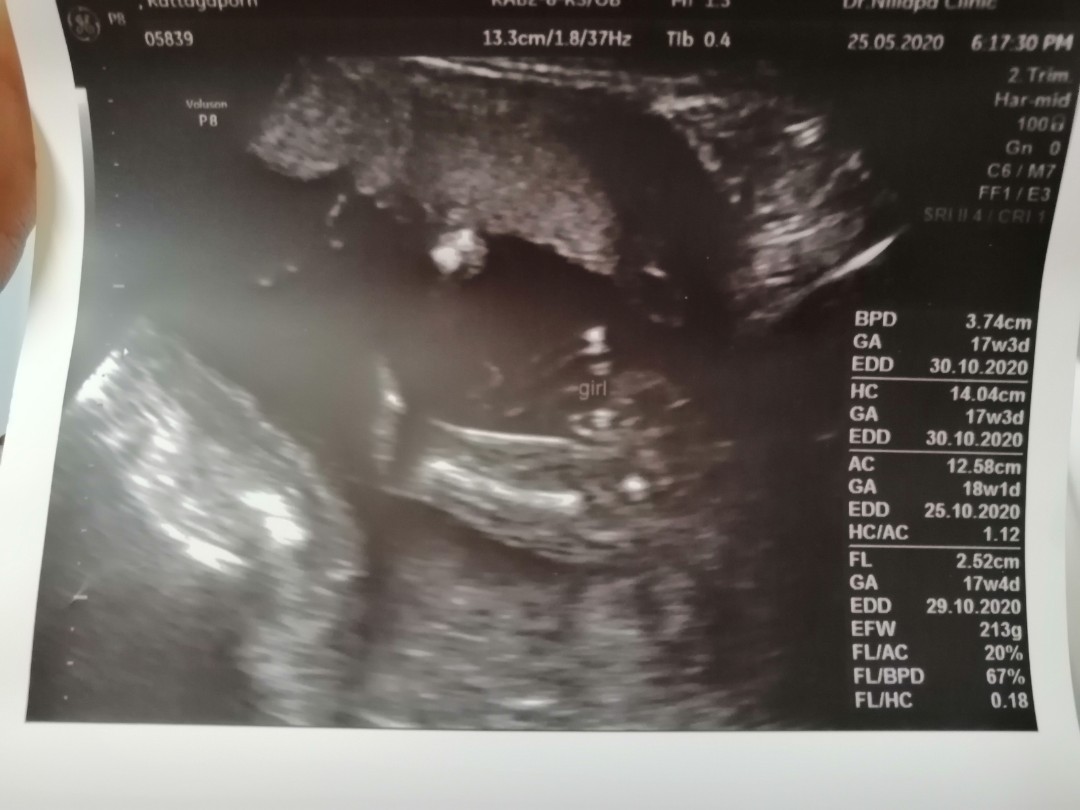

สดๆร้อนๆวันนี้เลยค่ะแม่ 17 วีคพอดี แถมน้องไม่หนีบเปิดให้แม่เห็น ถึงจะไม่ชัดเท่าไรเพราะหมอบอกว่าสายสะดือบัง แต่สาวน้อยของแม่ก็แอบโชว์แล้วค่ะ